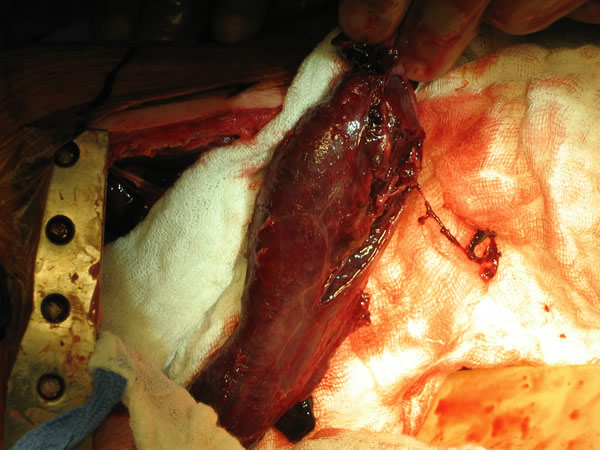

In the operating room, a right thoracotomy through the 5th intercostal space, 5th rib resection, and an intercostal muscle flap harvest was performed. Upon entering the chest, a large abscess was present surrounding the distal esophagus, with an empyema and widespread posterior mediastinitis. The esophagus exhibited full-thickness necrosis extending from the gastroesophageal junction to 5 cm below the thoracic inlet and was filled with clotted blood. There was a perforation of the distal esophagus extending from 10cm below the carina to the gastroesophageal junction (Figures 3A&B). The esophagus was resected with proximal and distal transections completed with an endoGIA 45 (3.5mm) stapling device. The posterior mediastinum was debrided and the right lung decorticated. Three chest tubes were placed, and a naso-gastric tube was placed within the cervical esophagus and both jejunostomy and gastrostomy tubes were placed. Forty eight hours later and off pressors, the patient was taken to the operating room for creation of a left cervical esophagostomy.

Figure 4: Histopathology reveals transmural acute and chronic inflammation with extensive ulceration and necrosis of the esophagus.